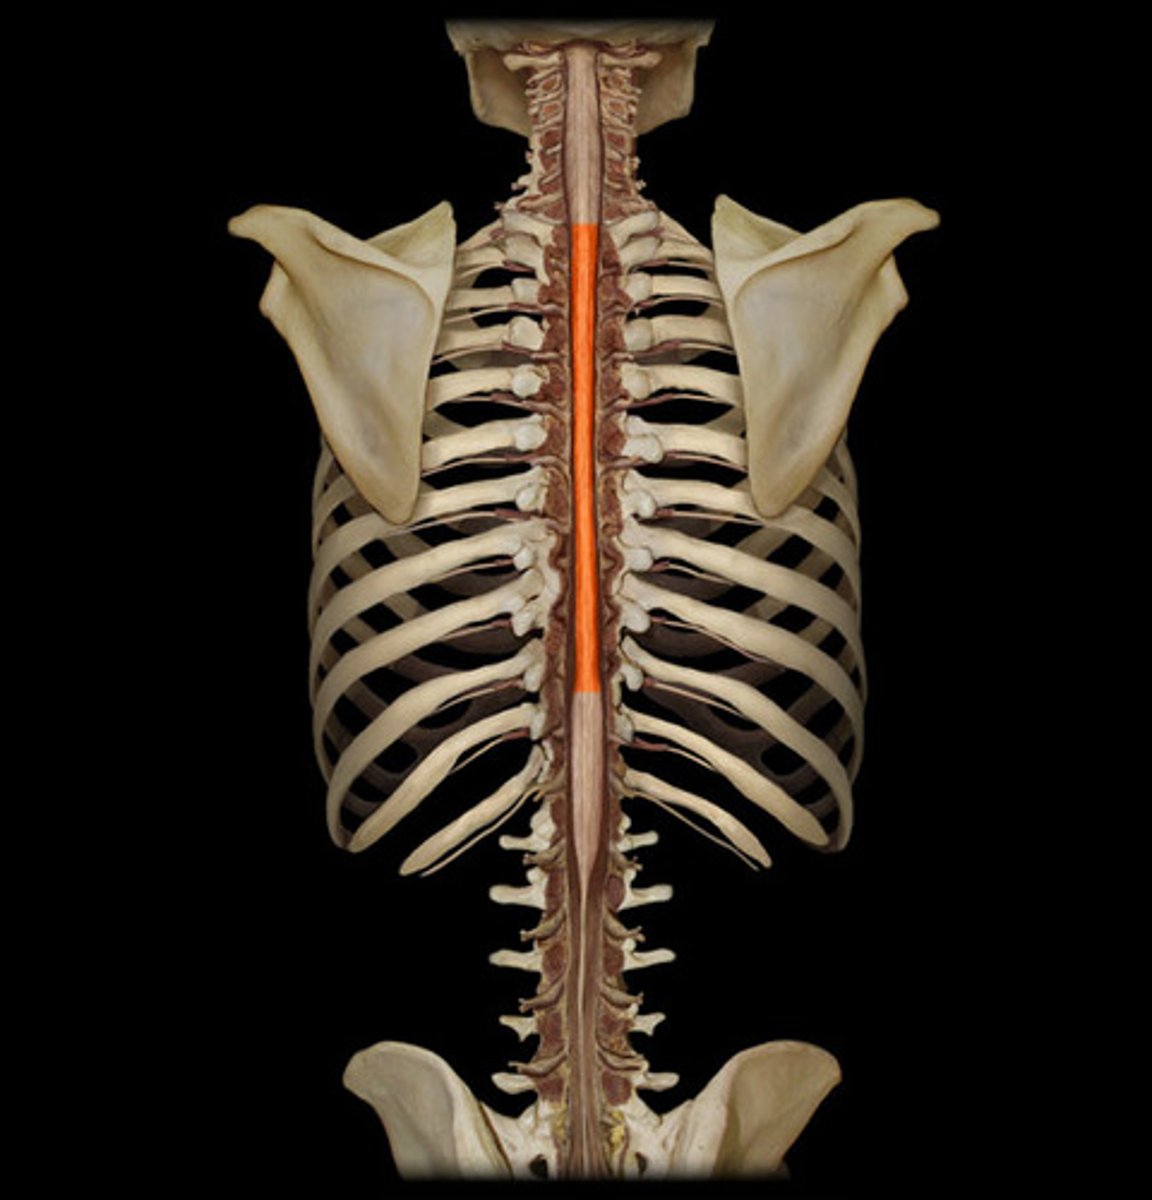

spinal cord

a major part of the central nervous system which conducts sensory and motor nerve impulses to and from the brain; housed within the vertebral canal

cervical region of spinal cord

supplies neck, shoulders, and upper limbs, C1-8

thoracic region of spinal cord

supplies thoracic cage, T1-12

lumbar region of spinal cord

supplies hips & front of lower limbs, L1-5

sacral region of spinal cord

supplies buttock, genitalia, and backs of lower limbs, S1-5

conus medullaris

inferior tapered end of spinal cord

cauda equina

collection of spinal nerves below the end of the spinal cord; below L1 vertebrae

filum terminale